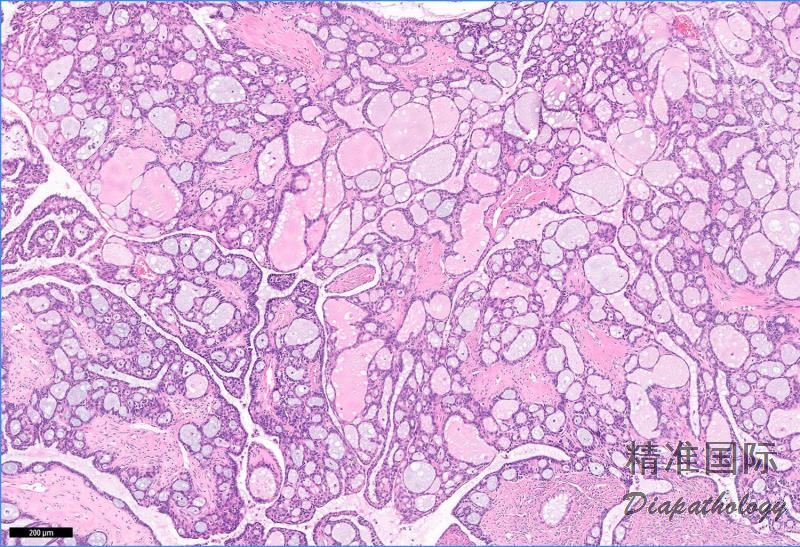

卵巢微乳头型浆液性交界性肿瘤/非浸润性低级别浆液性癌

Serous borderline tumour-micropapillary variant/Non-invasive low-grade serous carcinoma

由胞质少,中度核异型细胞增生形成非复杂分支的微乳头和/或筛状结构的非浸润性浆液性肿瘤。

特征性形态是从大的纤维性乳头放射状分出无数无分支的微小乳头,后者高度相当于其宽度的五倍;

微小乳头无或仅有少许间质轴心;

上皮细胞立方形或多边形,核浆比例增高,核小,大小形态一致,核仁小而突出,纤毛不明显;

核分裂像少,但多于交界性浆液性肿瘤;

一些肿瘤乳头表面呈筛状结构;

偶尔有肿瘤完全由筛状和/裂隙状腺体组成,缺乏微乳头结构;

交界性浆液性肿瘤也可见局灶微乳头/筛状结构,只有当 1 个融合性微乳头最大径大于 5mm,且细胞比交界性肿瘤明显异型时才可诊断非浸润性低级别浆液性癌,否则应诊断交界性浆液性肿瘤伴局灶微乳头结构。